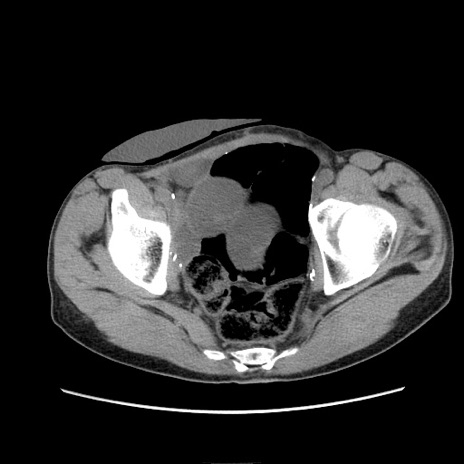

症例11(横断像)

【症例】 60歳代男性

【主訴】 下腹部痛

【現病歴】 本日夜中より下腹部痛の症状認め、受診。

【既往歴】 膀胱癌(膀胱全摘+尿管皮膚瘻術) 、胃癌術後

【身体所見】 BT 35.3℃、PR 58/min、BP 136/98mHg、腹部平坦、軟、腸蠕動音±、ストマ留置あり、左上腹部~正中部に圧痛あり、反跳痛なし。

【データ】WBC 5100、CRP0.01